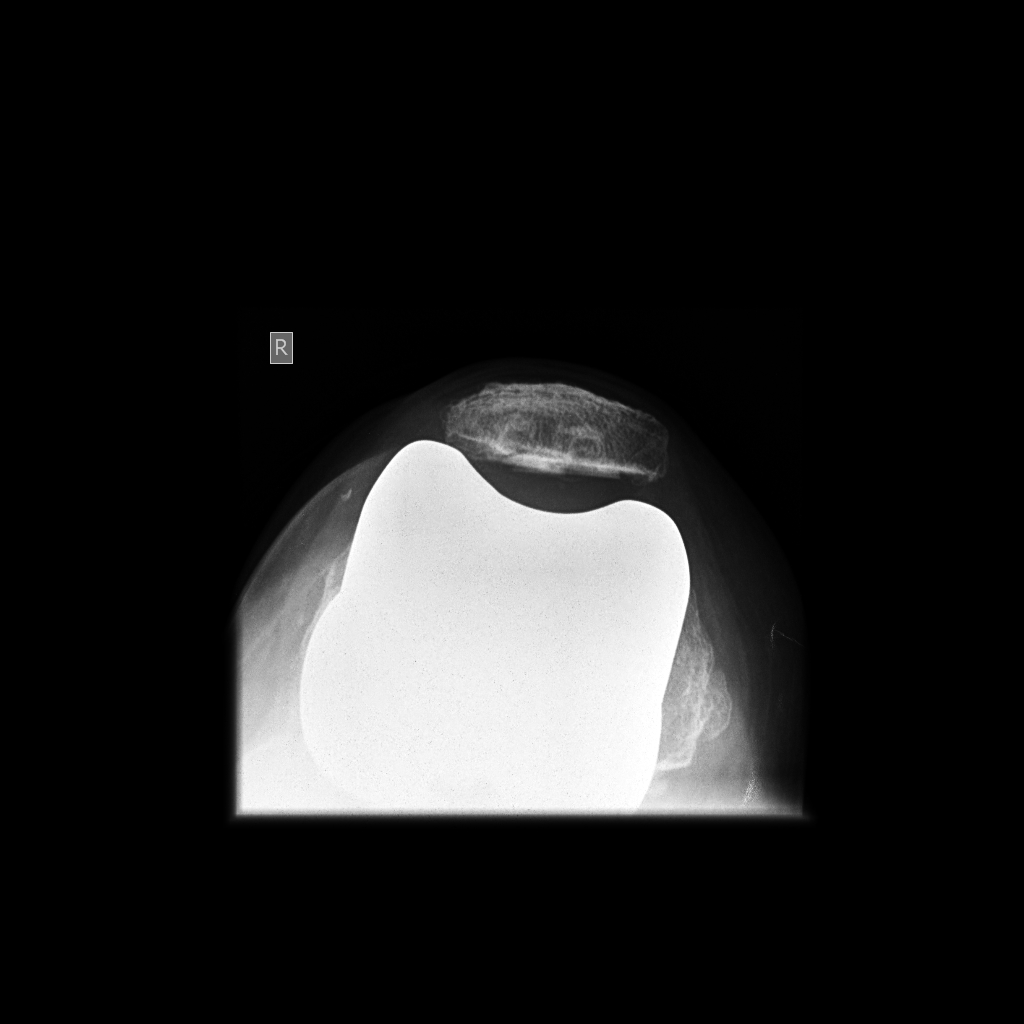

From radiopaedia.org

Patellar enthesopathy Image Floating Patella Syndrome patients who have a tracking problem in the patellofemoral joint, where the patella (kneecap) does not stay in the groove on. patellar subluxation, or a dislocation of the knee cap, requires a diagnosis and treatment from a doctor. patellar instability is a condition characterized by patellar subluxation or dislocation episodes as a result of injury, ligamentous laxity.. Floating Patella Syndrome.